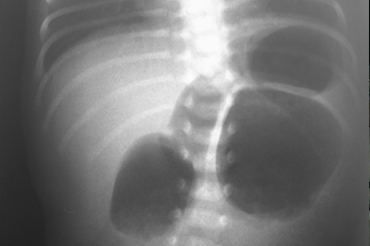

Atresia Intestinal

Neonatal y Lactante